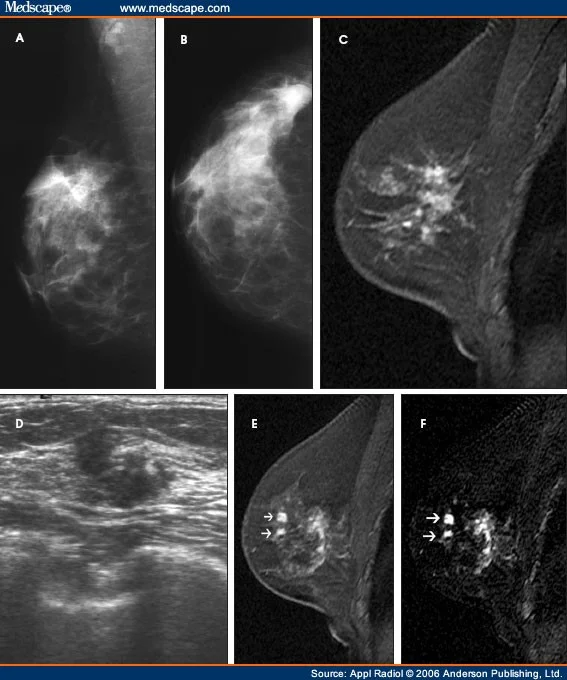

The spider web-like mass found in my right breast the summer of 2012 had me thinking about my mom, the farm she was raised on, DDT, Rachel Carson, and Cannabis - in that order.

I saw the configuration while proactively peeking over the shoulder of both the mammogram and ultra-sound technician.

While waiting for the biopsy I decided to do some research and easily found an image of a nearly identical mass on the Mayo Clinic’s Web site, naming it, “Lobular Carcinoma.”

This type of cancer begins in the milk-producing glands of the breasts or lobules, affecting 10 to 15 percent of all women in the U.S. It's a mass, not a lump, as with Ductal Carcinoma, affecting up to 85 percent of women in this country, annually. And cannot be mistaken for a cyst.

lobular carcinoma is a breast cancer that affects 10-15 percent of women in the U.S. It's a spider-web-like mass, not a tumor that could be mistaken for a cyst.

Happily the second scheduled biopsy found nothing, with the mass completely gone from both the mammogram and ultra-sound. The attending technician called it a “technical error,” stating the initial technician probably got it wrong. But I was there looking over her shoulder and saw the same distinct spider-web mass in both the mammogram and ultra-sound.